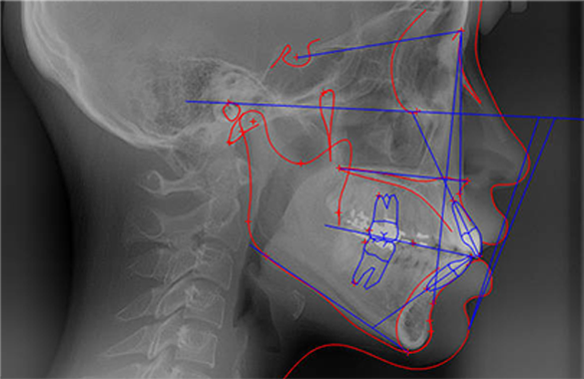

º´¿øÀ» ¹æ¹®ÇÏ¿© ¾ó±¼ »À X-RAY¿Í Ä¡¾ÆºÐ¼®, ¾ó±¼ À±°ûÀ» º¸°í ¹®Á¦Á¡À» ºÐ¼®ÇÏ°Ô µË´Ï´Ù.

Áø´Ü°ú ºÐ¼®À» ÅëÇÑ È¯ÀÚ °³°³Àο¡ ¸Â´Â ¼ö¼ú¹æ¹ýÀÌ Á¦½ÃµÇ°í »ó´ã ÈÄ ¼ö¼ú °èȹÀ» ¼¼¿ì°Ô µË´Ï´Ù.

- Á¤È®ÇÏ°í °úÇÐÀûÀÎ ºÐ¼®À» ¹ÙÅÁÀ¸·Î Á¾ÇÕÀûÀÎ ¼ö¼ú °èȹÀ» ¼¼¿ì°í, ¼ö¼ú Àü, ȯÀÚ¿ÍÀÇ ÃæºÐÇÑ »ó´ãÀ» ÅëÇØ ¸¸Á·½º·¯¿î ¼ö¼ú °á°ú¸¦ ¾òÀ» ¼ö ÀÖ½À´Ï´Ù.